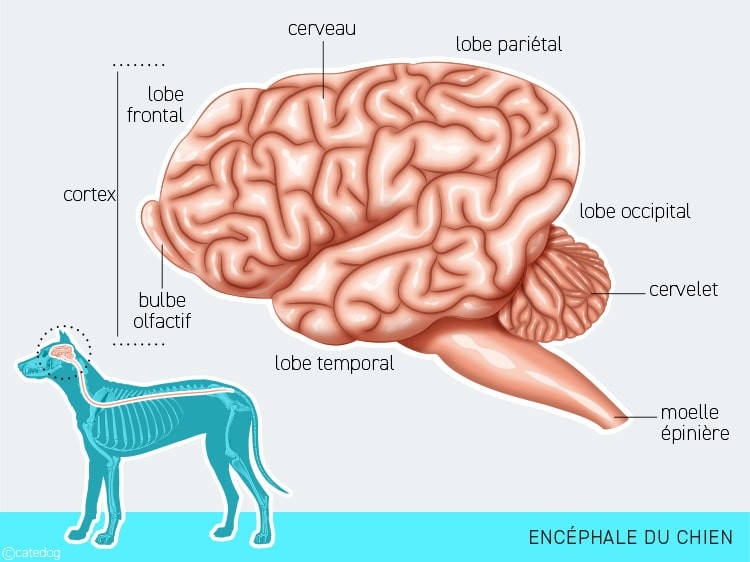

Neurologie canine : Comprendre les troubles du système nerveux chez le chien

Neurologie canine : Comprendre les troubles du système nerveux chez le chien

Neurologie canine : Comprendre les troubles du système nerveux chez le chien

Neurologie canine : Comprendre les troubles du système nerveux chez le chien